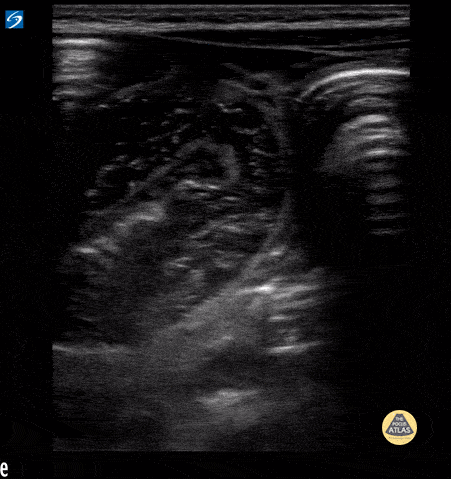

Small bowel obstruction with to and fro peristalsis visualized. Contributor: Peter Gutierrez, MD FAAP FACEP; Children's Healthcare of Atlanta; @pocuspete